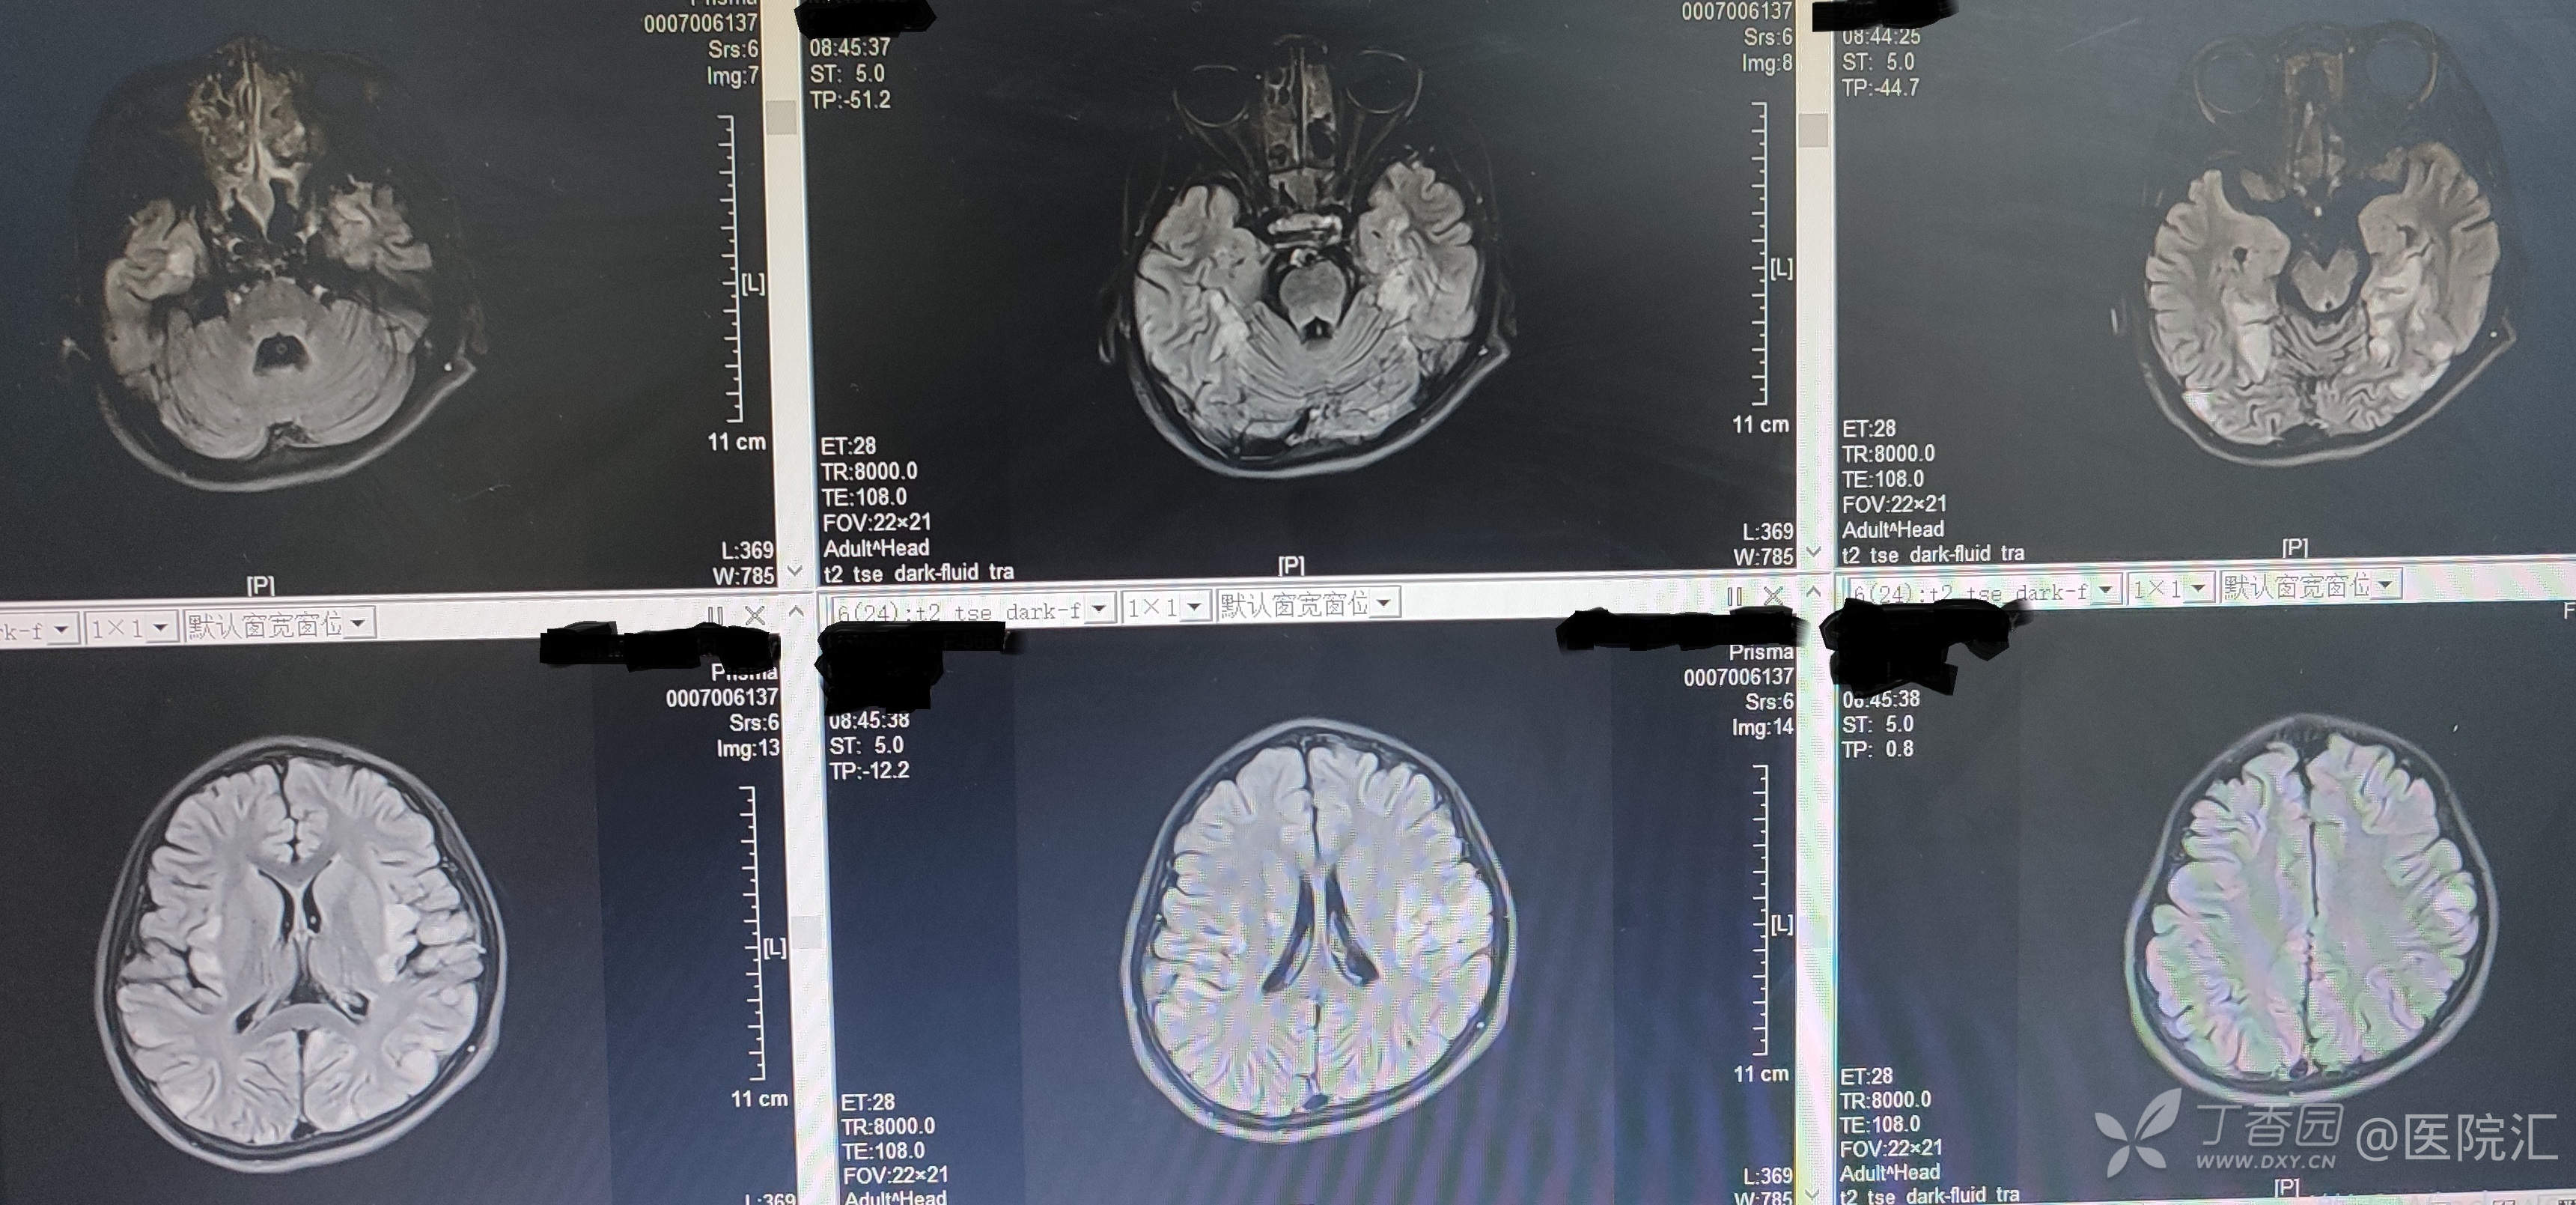

头颅MR:双侧大脑半球异常信号,脑炎?

图2 -3患儿头颅MR表现